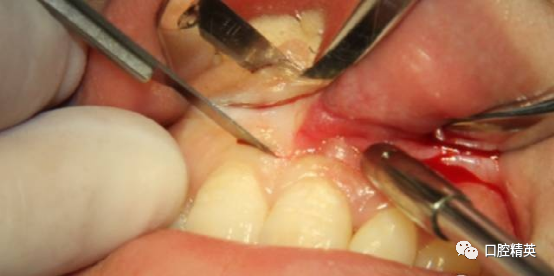

术前检查已知唇侧骨开窗,囊壁与软组织瓣会出现粘连,采用锐性分离,轻柔分开组织瓣并彻底清理瓣内侧。

初步分离后可见较厚的囊壁暴露,夹持后分离囊壁与骨面,争取完整分离。